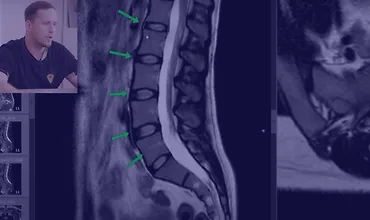

Как читать МРТ поясницы

На множестве примеров изображений вы научитесь распознавать грыжу, протрузию, стеноз позвоночного канала, компрессию нервных корешков, жировую дегенерацию мышц и спазмы мышц при наличии грыжи. Вы узнаете, как возникает поясничный прострел и многое другое. Регулярно анализируя МРТ своих пациентов и сопоставляя полученные данные с их жалобами, вы сможете все лучше понимать причины их болевых ощущений.